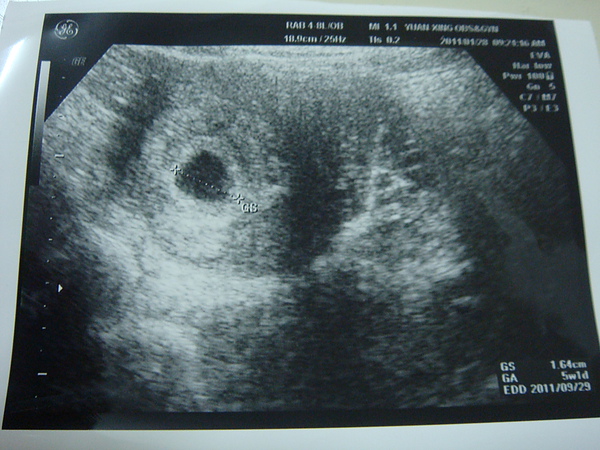

因為陳先生很心急 所以只好去看婦產科了 短短幾天內一直驗孕XDD

一直很討厭驗尿這件事 雖然我平常很厚尿 但是叫我要尿偏偏很難擠出來XDD

所以這次擠出來的還真的剛剛好勉強通過底線 哈哈

一進去診間 林醫師就笑著說"恭喜你喔~ 已經懷孕了" (.....不然我來幹嘛 哈)